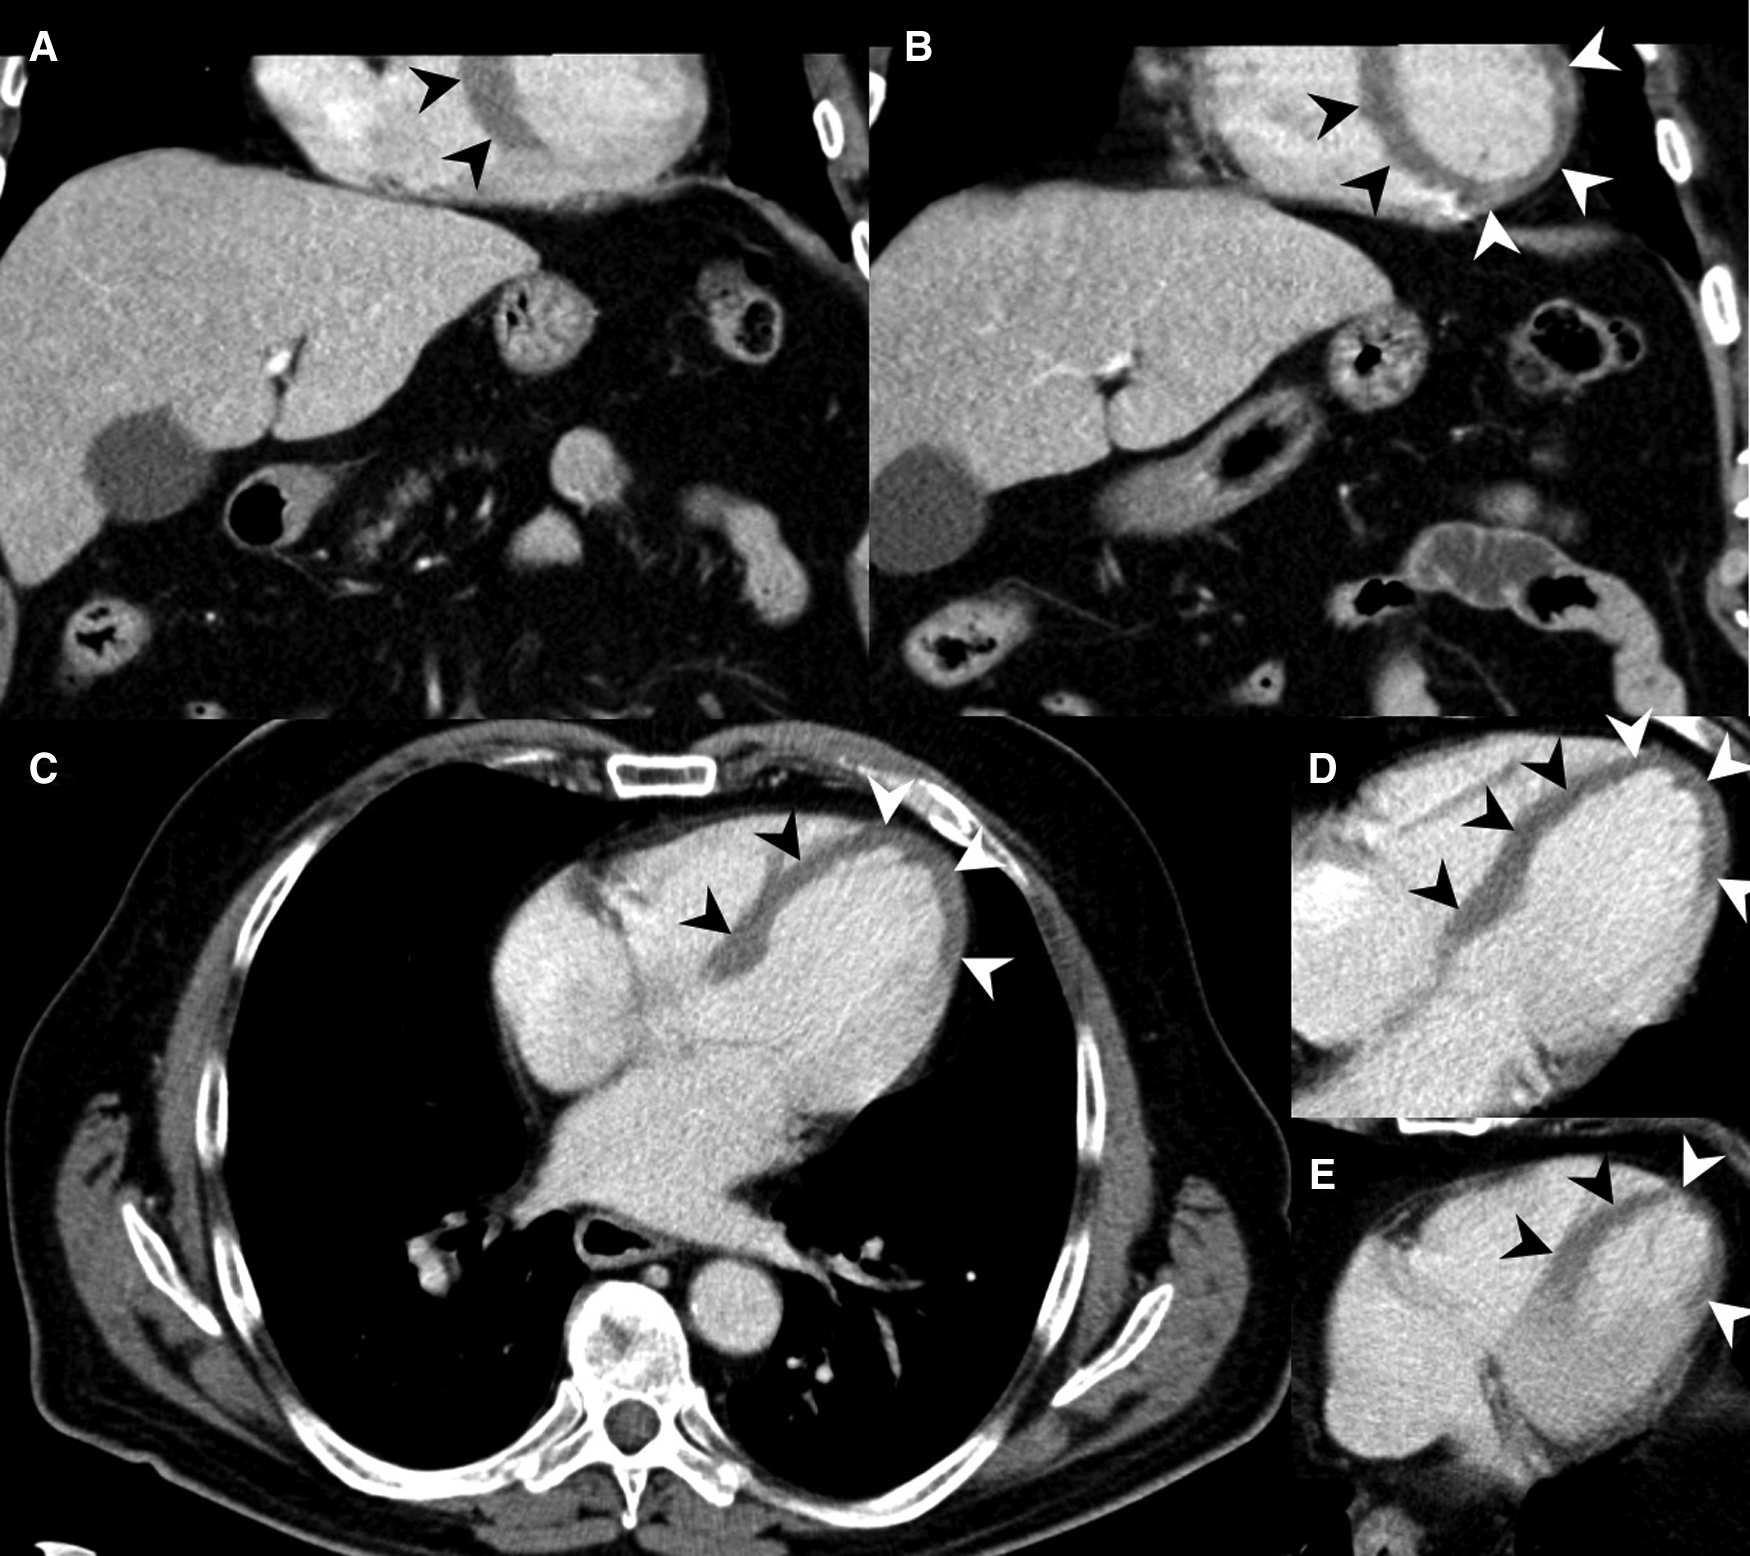

Figure 5

73-year-old male with acute MI, evident as MH on MDCT (arrowheads). (A,B) Coronal reformations show large areas of MH in the left ventricle. (C–E) MH shown at the interventricular septum and the heart apex in axial slices. The patient deceased after PTCA.

Figure 6

MDCT examination of a 43-year-old male, who was required to be resuscitated in the emergency room with suspected pulmonary embolism. The patient was referred for MDCT with a delay of three hours. The abdominal MDCT series showed MH (arrowheads) in the vascular territory of the left anterior descending artery (LAD) in axial slices (A,B) and coronal reformations (C), which was immediately communicated to the treating physicians. Stents were placed in both coronary arteries during emergency PTCA. The patient died two days later as a result of his MI.